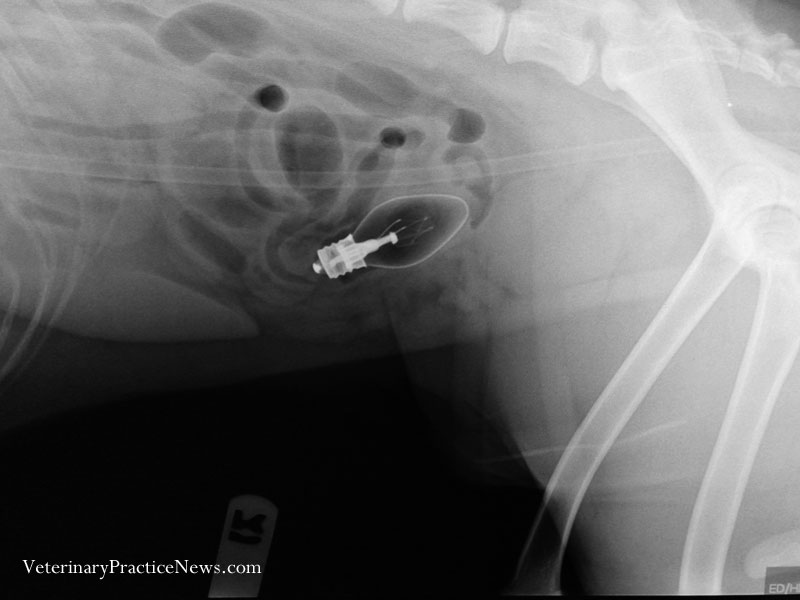

收好你的襪子、黃色小鴨跟燈泡!不然它們會出現在你家毛小孩胃裡!